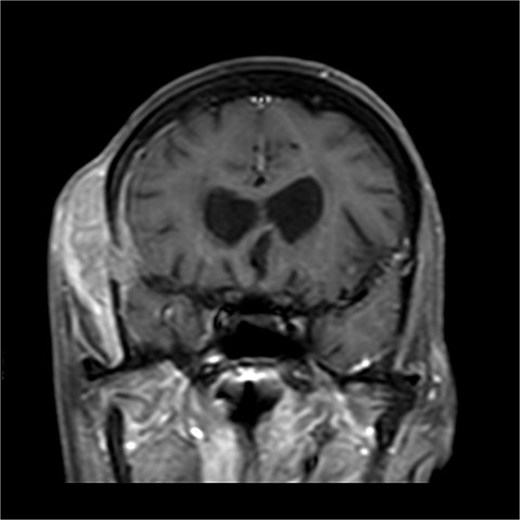

A 70-years old female came to the tertiary hospital, with a gradually enlarging right frontal-temporal scalp swelling associated with headache. She presented to the ER with abnormal movement, described by the son was gazing upward toward specific point with right upper limb jerky movement lasting for 15 s and frothy secretions, not responding during the event. Whole event lasted for 40–45 s. No reported pre-event symptoms and for post event patient was back to baseline after one-to-one hour and half. The son noticed this event repetitively happens on exertion, positioning the patient from lying to siting position, and before the dialysis sessions. Regarding her surgical and medical history, she is a known case of type 2 diabetes mellitus, hypertension, end-stage renal disease on dialysis, and cardiac disease with low ejection fraction. In addition, the patient had undergone a total abdominal hysterectomy with bilateral salpingo-oophorectomy under spinal anaesthesia in for endometria carcinoma, stage IB, grade 2 and subsequently received vaginal vault brachytherapy. Upon physical examination, the patient was noted to have a large, non-tender, soft to firm swelling in the right frontal-temporal region, with no other remarkable findings. CT with contrast (Figs 1 and 2) of the brain revealed metastasis to the right frontal bone and the greater wing of the sphenoid, with large extra-cranial and small intracranial soft tissue components with no parenchymal brain lesions were observed. A brain biopsy confirmed that there was fibromuscular and adipose tissue with focal necrosis and atypical cells, with crushed and scarse atypical cells likely neoplastic or reactive. Also, PET CT scan (Figs 3 and 4) confirms that there was brain metastasis sparing lymph nodes. Given her poor status and significant comorbidities, she was deemed unfit for systemic chemotherapy. The patient received palliative radiotherapy to the scalp lesion 20 Gy in 5 fractions.

FDG uptake was noted in the scalp lesion, while no other areas of abnormal uptake were identified elsewhere.